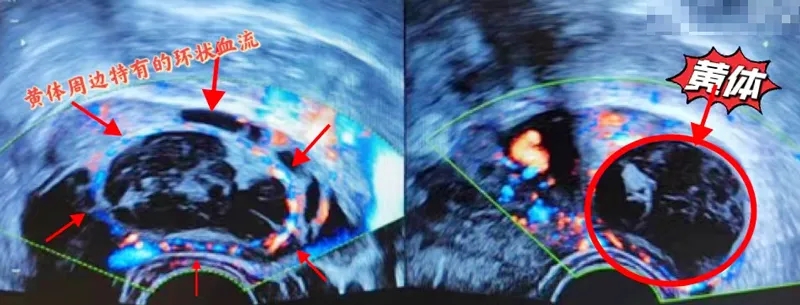

什么是黃體呢?

在女性的身體里

每個月都會有一顆卵子

成熟并排出

卵子排出后

卵泡壁就會轉(zhuǎn)變?yōu)辄S體

一般在排卵后一周左右

黃體發(fā)育到最大

有的能長到5到8厘米

這時候如果去做B超

可能就會看到一個囊腫

這就是黃體囊腫

它其實(shí)是一種生理性囊腫

為什么會發(fā)生黃體破裂呢?

當(dāng)黃體發(fā)育到巔峰時期

里面有著豐富的毛細(xì)血管

但它的壁卻非常薄